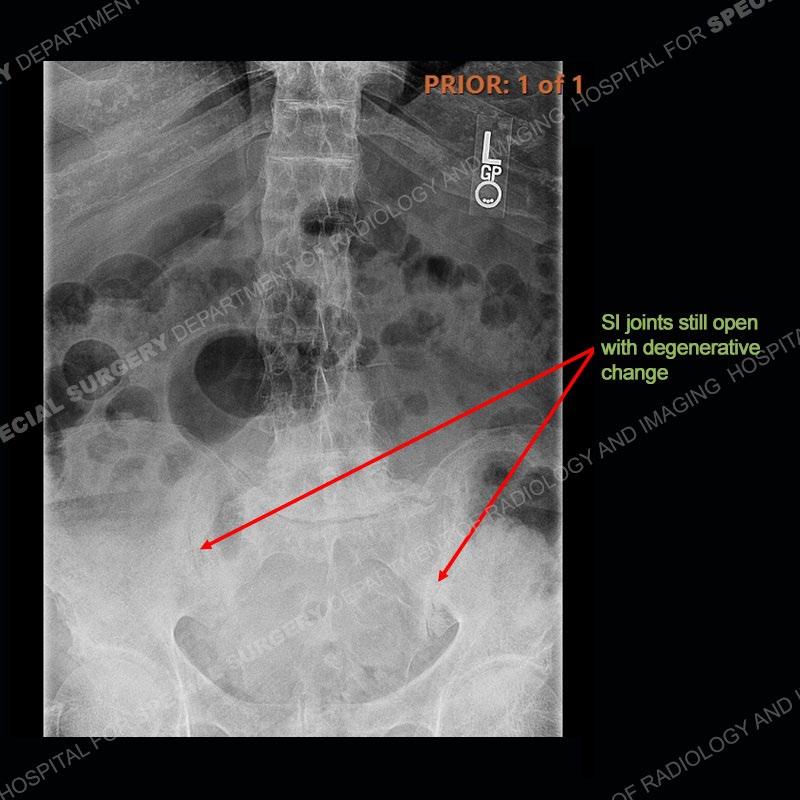

There is severe degenerative change of the left hip. The lumbar and thoracic spine show calcification of the intervertebral discs, loss of disc space, and bulky bony bridging across the disc spaces. Of important note is that the sacroiliac joints are open. They show advanced degenerative changes but not findings of an inflammatory arthritis. Bilateral knee arthroplasties are present and there are severe degenerative changes of both glenohumeral joints.

In comparison to ankylosing spondylitis (AS) where there are thin syndesmophytes of the outer annulus, this bony bridging tends to be bigger and bulkier. In addition, at this stage of AS the sacroiliac joints would be fused, but in ochronosis as seen here, the SI joints are open although with severe degenerative changes. No erosions are present of the SI joints, just advanced degenerative changes. This patient was treated with a left total hip arthroplasty and the black deposition of oxidized homogentistic acid of the cartilage is well shown.